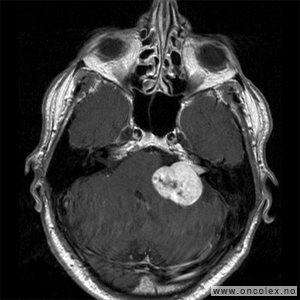

Vestibularisschwannom

Av hjernenervesvulstene er det vestibularisschwannom som er vanligst. Schwannomer kan forekomme på flere hjernenerver, men er i de fleste tilfeller altså lokalisert til balansedelen av hørsels- og balansenerven (åttende hjernenerve). Vestibularisschwannom diagnostiseres vanligvis i 40–50 års alder og er noe hyppigere hos kvinner enn hos menn. Nesten alle vestibularisschwannomer er godartede og vokser langsomt. Hos 5 % av pasientene finner man vestibularisschwannom på begge sider. Disse pasientene har per definisjon nevrofibromatose type 2.